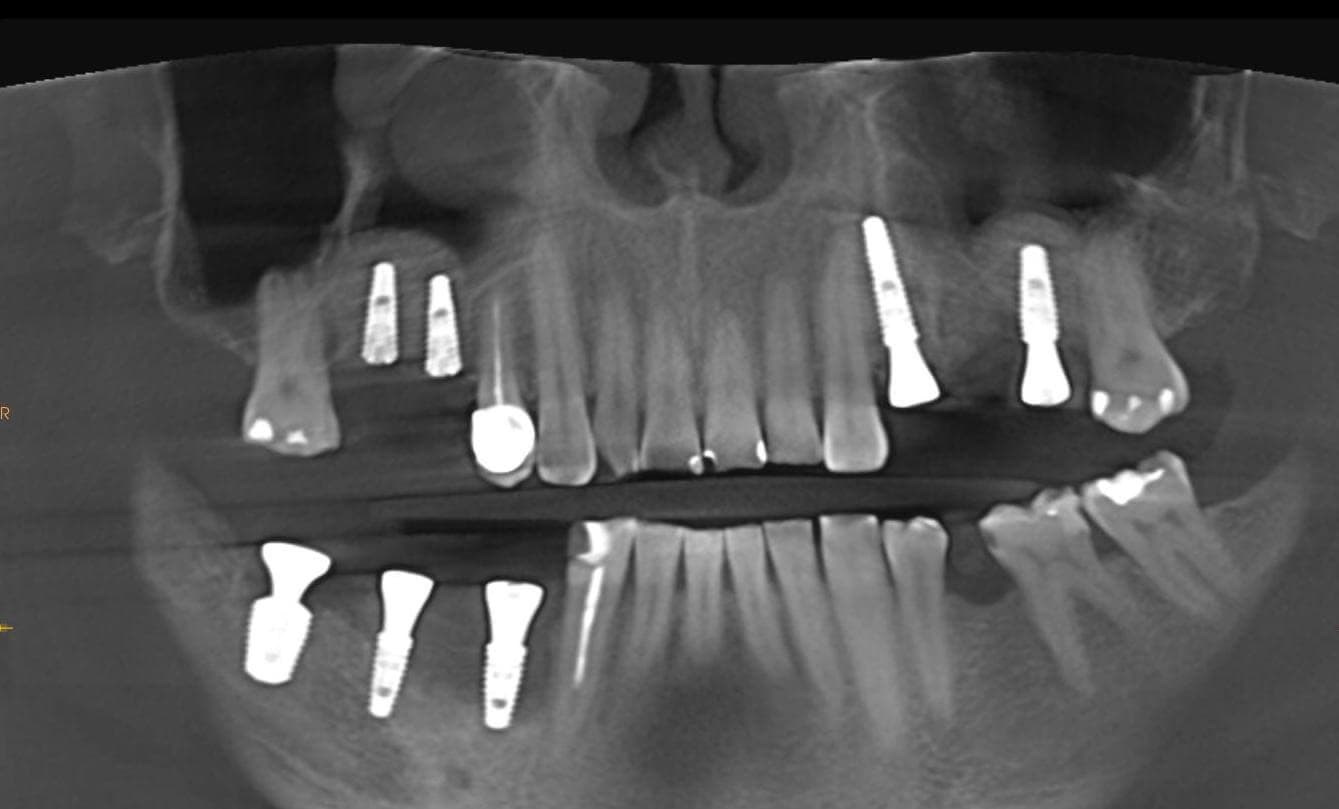

A male patient came to us with complaints of missing teeth in the posterior regions of both the lower and upper jaws, as well as severe wear of the remaining front teeth.

In the first stage of treatment, we performed surgical preparation: bone grafting in the upper jaw (sinus lift), implant placement, and soft tissue grafting in areas where there was a significant deficiency.

After six months, following digital planning of the future restorations, zirconia crowns and bridge prostheses on implants were placed in the posterior regions, and the worn remaining teeth were restored with ceramic veneers.